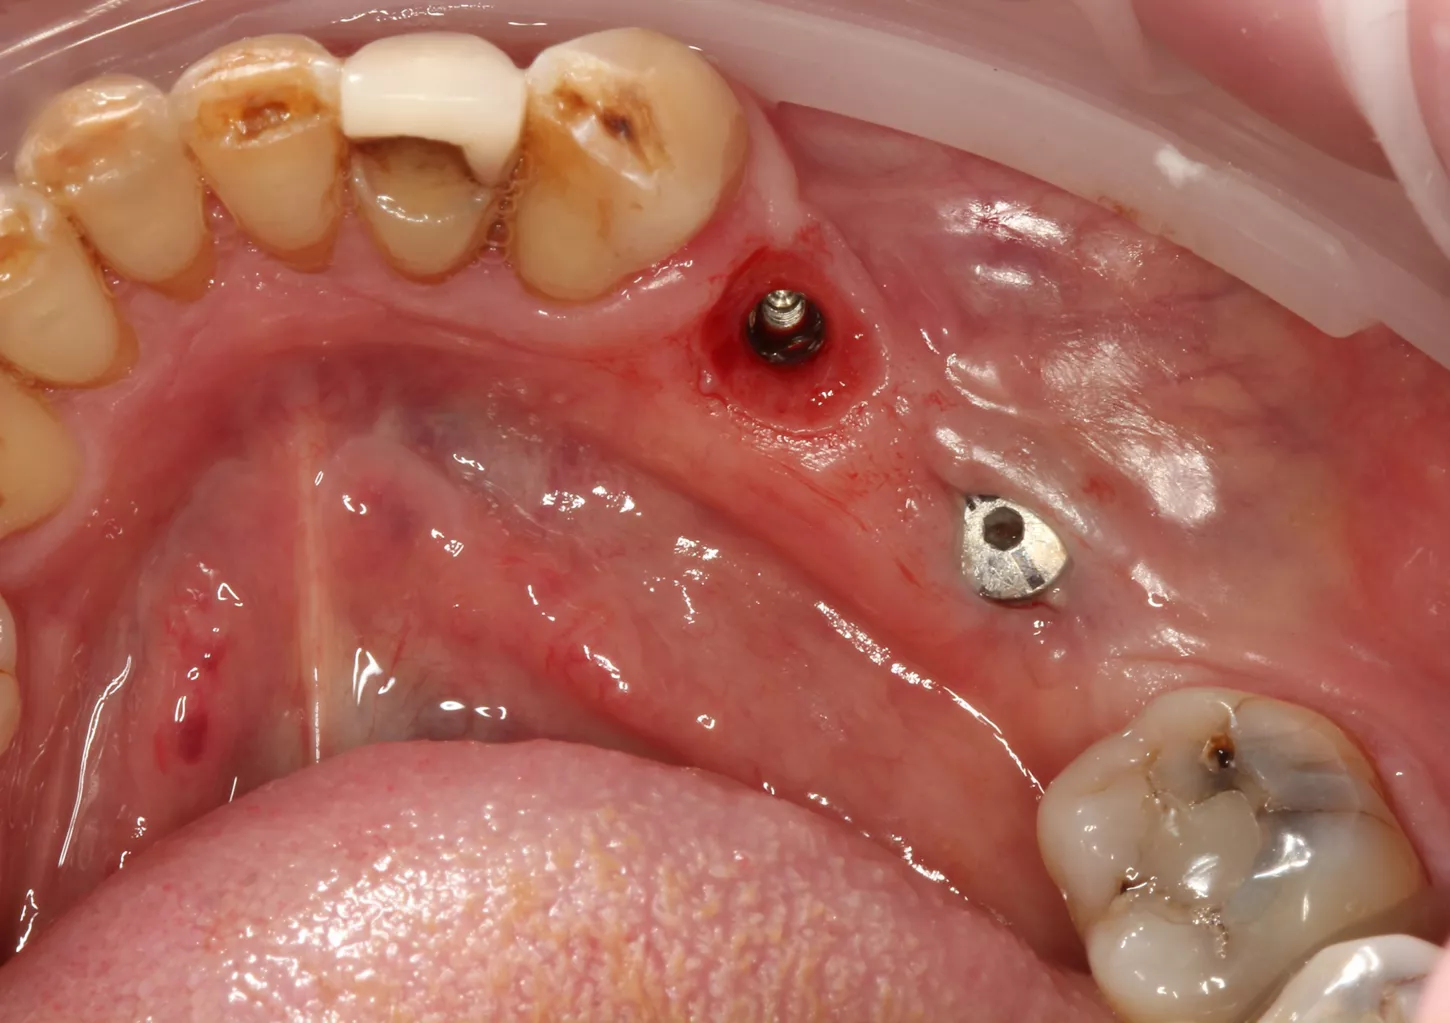

7. Distal implant placed with a cover screw, and mesial implant restored with a HealFit® SH anatomical healing abutment.

7

Suturing was adapted to each implant site. The distal implant was fully submerged with a cover screw, requiring complete primary closure. At the mesial implant, where a HealFit® SH abutment was placed, only two simple interrupted sutures were placed mesially and distally to stabilize the soft tissues.

8. Suturing was adapted to each implant site. The distal implant was fully submerged with a cover screw, requiring complete primary closure. At the mesial implant, where a HealFit® SH abutment was placed, only two simple interrupted sutures were placed mesially and distally to stabilize the soft tissues.